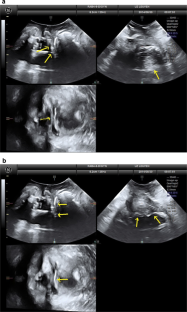

There were 17 women in the PP and 25 in the PVDF mesh group, without differences in baseline demographics. None had significant prolapse, recurrence, symptoms, or complications. On TPUS, mesh was visible in all patients both caudally (perineal) and cranially but was more echogenic in the PVDF mesh group. Mesh length from distal to proximal that was visible on TPUS was longer for PVDF mesh, for both anterior and posterior vaginal arms (all P < 0.05), and for mesh above the vaginal apex (P = 0.002). The inferior aspects of the mesh showed areas of double mesh layers, suggesting folding in 80% of women in both groups, without symptoms.